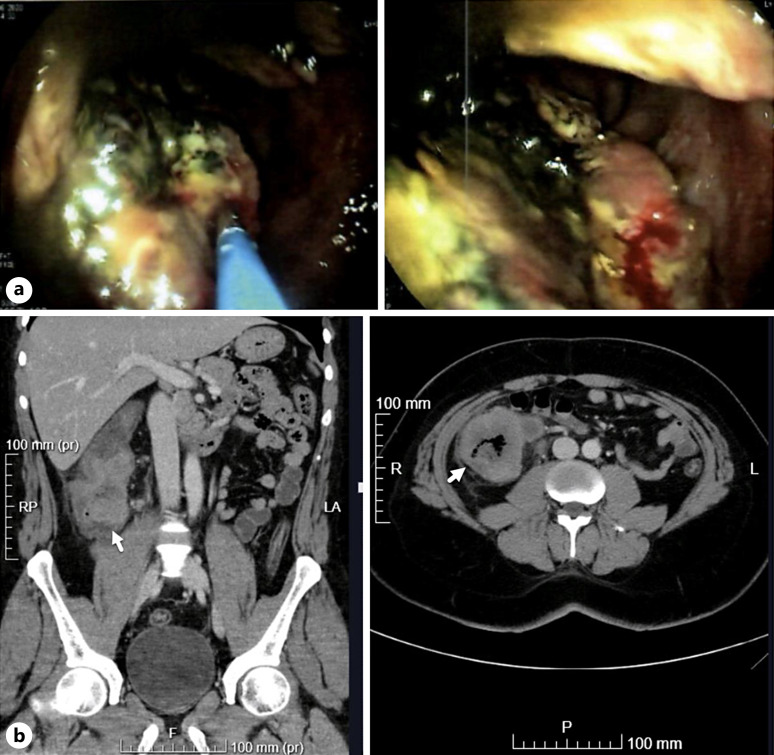

Case presentation: We present a 39-year-old male with a 9-year history of UC who experienced severe anemia and hematochezia. Imaging and histopathological analysis confirmed a diagnosis of stage IIIB ASC of the right colon. The patient underwent total colectomy followed by adjuvant chemotherapy (XELOX), ileoanal pouch reconstruction, and stoma closure. After 56 months of follow-up, he remains disease-free with good pouch function.